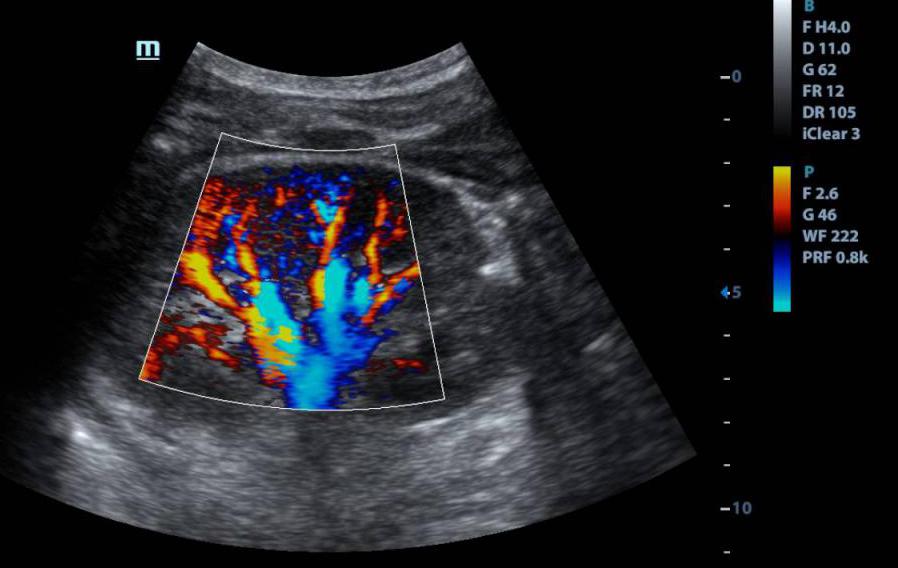

Нейросонография — это ультразвуковое исследование головного мозга, которое проводится через родничок. Пока у ребёнка не закрылся мягкий участок на темечке, через него можно смотреть прямо в мозг: без наркоза, без облучения, без боли. Исследование входит в плановый чек-ап в один месяц, а при необходимости может проводиться с первых часов жизни.

НСГ можно делать вплоть до года, пока открыт большой родничок. После его закрытия, примерно в 12-18 месяцев, стандартный доступ через родничок становится невозможным. Однако существует транскраниальная нейросонография — исследование через височные кости черепа, которые остаются достаточно тонкими для прохождения ультразвука и в более старшем возрасте. Этот метод позволяет оценить состояние желудочковой системы и кровоток, но его информативность ниже: тонкие изменения субарахноидальных пространств он уже не покажет. При необходимости полноценной визуализации после закрытия родничка используется МРТ, которое требует медикаментозной седации у детей раннего возраста.

Ликвор — спинномозговая жидкость. Она омывает мозг снаружи и циркулирует внутри: питает, защищает, выводит продукты обмена. В норме её количество строго сбалансировано: вырабатывается, циркулирует, всасывается. Если баланс нарушен, жидкости становится больше, чем нужно. И это видно на НСГ.

- Наружное расширение: ликвор скапливается снаружи мозга, между корой и оболочками, расширяется субарахноидальное пространство, увеличивается межполушарная щель. Часто сопровождается ускоренным ростом окружности головы. Врачи нередко квалифицируют это как «доброкачественное» и рекомендуют наблюдение. Иногда так и есть. Но это не означает, что наблюдение можно вести формально.

- Вентрикуломегалия: расширение желудочков мозга — внутренних полостей, где ликвор вырабатывается и откуда должен оттекать. Это другой механизм и другой уровень настороженности. Желудочки расширяются, когда нарушен отток или повышено давление изнутри.

Когда присутствуют оба варианта одновременно, система циркуляции ликвора работает с нагрузкой на нескольких уровнях сразу.